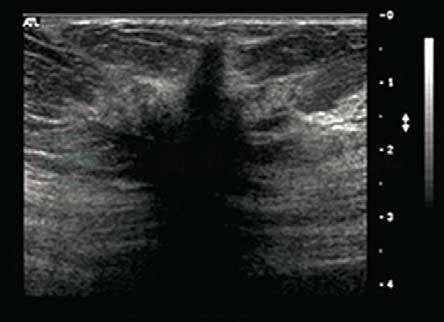

七、正常乳腺超声表现

由浅至深,正常乳腺的声像图由皮肤、皮下脂肪层、腺体层组成,乳腺后方为乳腺后间隙和胸壁结构(图5-2)。乳腺随年龄和生理状态的变化主要表现在脂肪和腺体的变化,通常,随着年龄增加,腺体内终末导管和腺泡萎缩,腺体变薄,回声增高,皮下脂肪和乳腺后间隙脂肪相对增多。

图5-2 正常乳腺的声像图

由浅入深分别是皮肤、皮下脂肪层、腺体层和胸壁肌层等,箭头示浅筋膜浅层